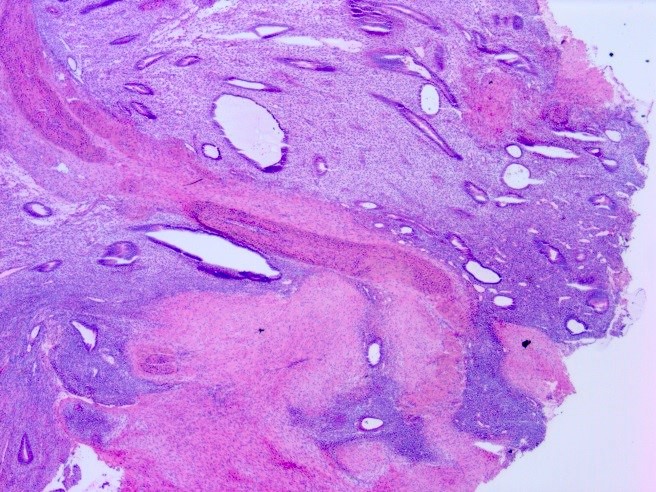

Microscopic (histologic) description

- At least 2 of the following 3 features

- Endometrial type glands

- Müllerian type epithelium (can be atrophic to cycling endometrium)

- Can show degenerative atypia (enlarged smudgy nuclei) or metaplasia

- Endometrial type stroma

- Often contains fine capillary network

- May undergo smooth muscle metaplasia, fibrosis (longstanding), decidual change

- May be myxoid (particularly in pregnancy)

- Stroma may be the only identifiable component (stromal endometriosis)

- Evidence of chronic hemorrhage (hemosiderin laden or foamy macrophages)

- Endometrial type glands

Microscopic (histologic) images